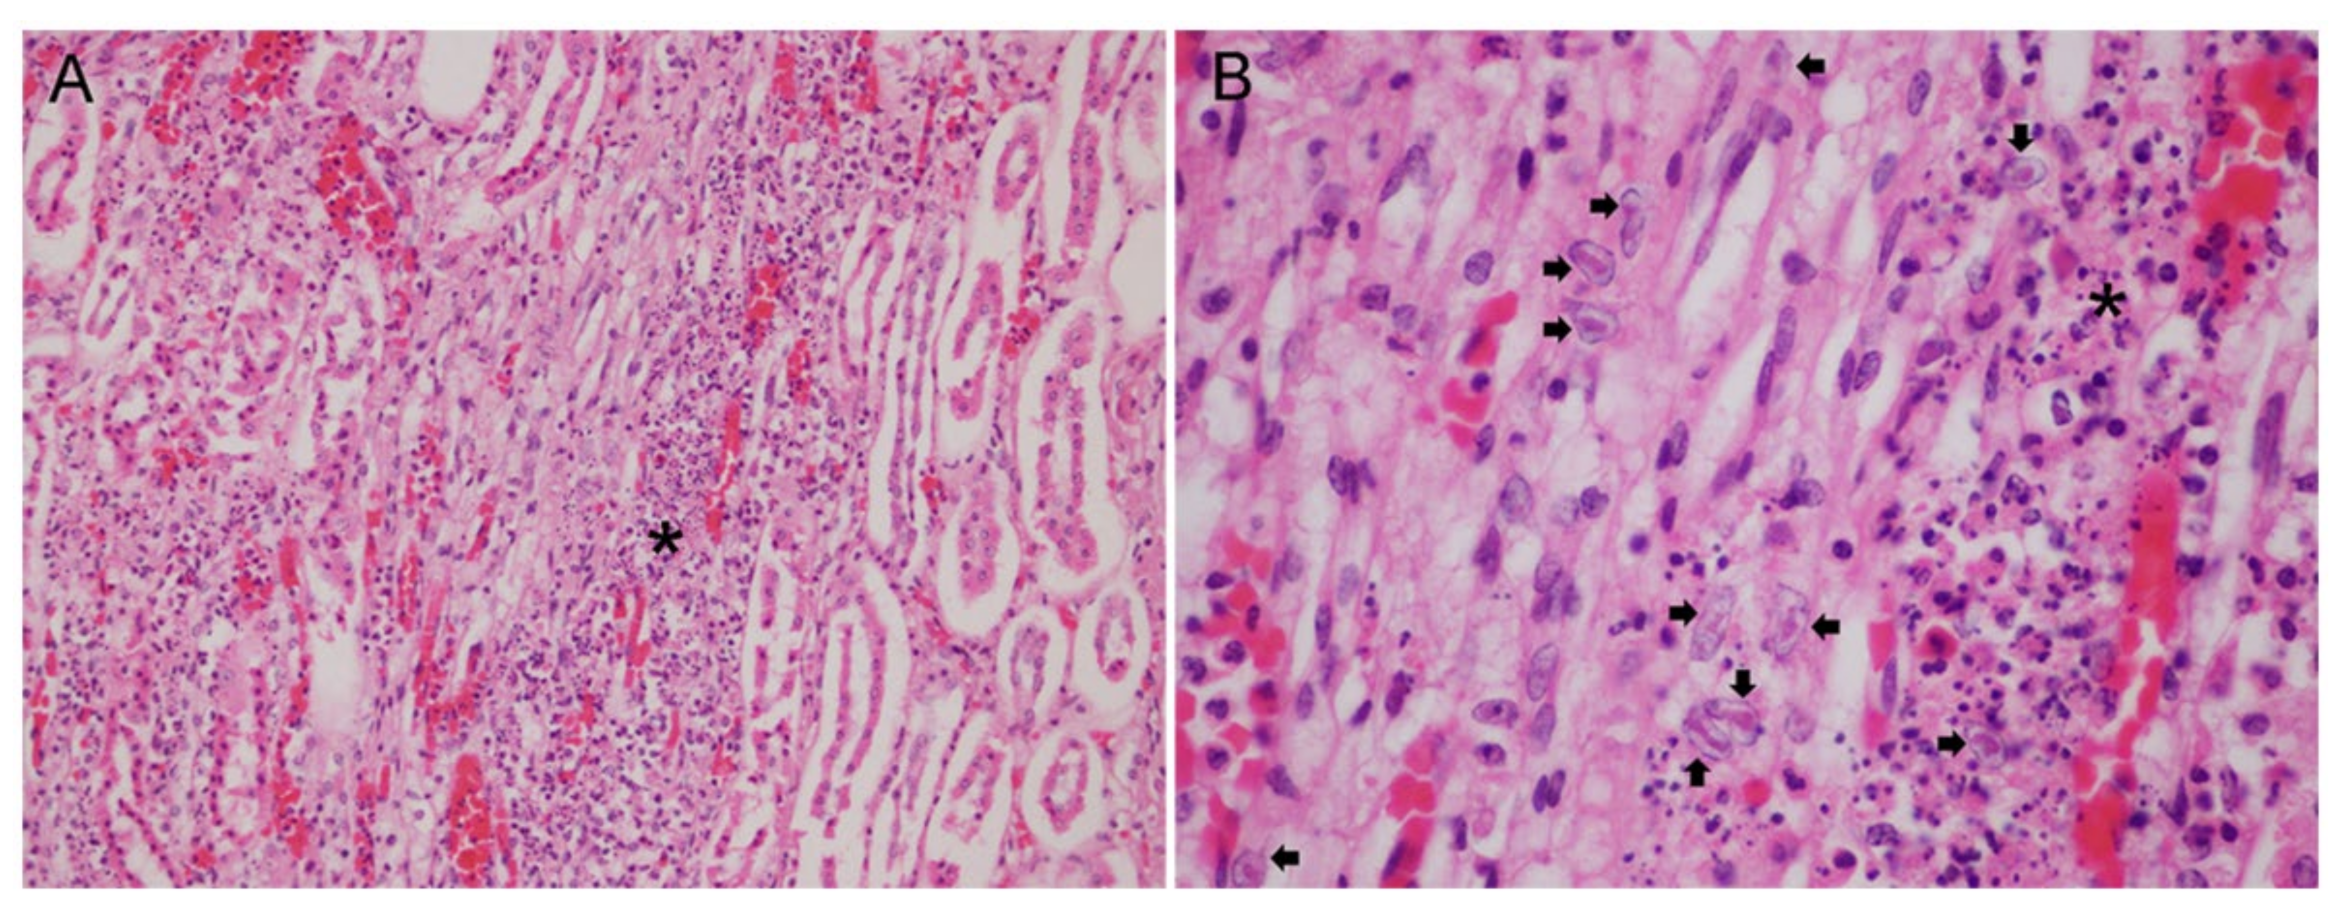

3.2. Gross and Histopathological Findings